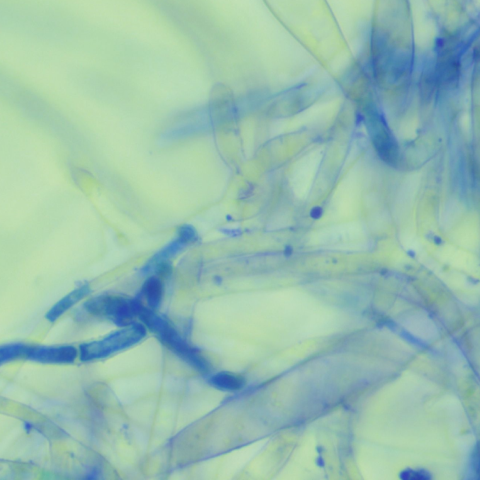

¼¼±ÕÀ̳ª °õÆÎÀÌ °¨¿°¿¡ ÀÇÇØ ÀϾ´Â ¿ÜÀÌ¿°, ÇǺο°Àº ¾ÆÀ̵鿡°Ô ¸Å¿ì ÈçÇÑ ÁúȯÀÔ´Ï´Ù. ´«¿¡ º¸ÀÌ´Â ¿°Áõ Ä¡·á »Ó¸¸ ¾Æ´Ï¶ó, ÇǺο°À» ¹ß»ý½ÃŰ´Â ¿ø¹ß Áúȯ ±îÁö Áø´Ü°ú °ü¸®°¡ Áß¿äÇÕ´Ï´Ù.

ÇǺΠµµ¸»°Ë»ç, °õÆÎÀÌ ¹èÁö °Ë»ç µîÀ» ÅëÇØ °¨¿°ÀÇ ¿øÀÎÀ» ã¾Æ¾ß ÇÕ´Ï´Ù. ¾Ë·¯Áö°¡ ÀǽɵǸé Ç÷¾×°Ë»ç¸¦ ÅëÇØ ¾Ë·¯Áö °Ë»ç¸¦ ÁøÇàÇÕ´Ï´Ù.